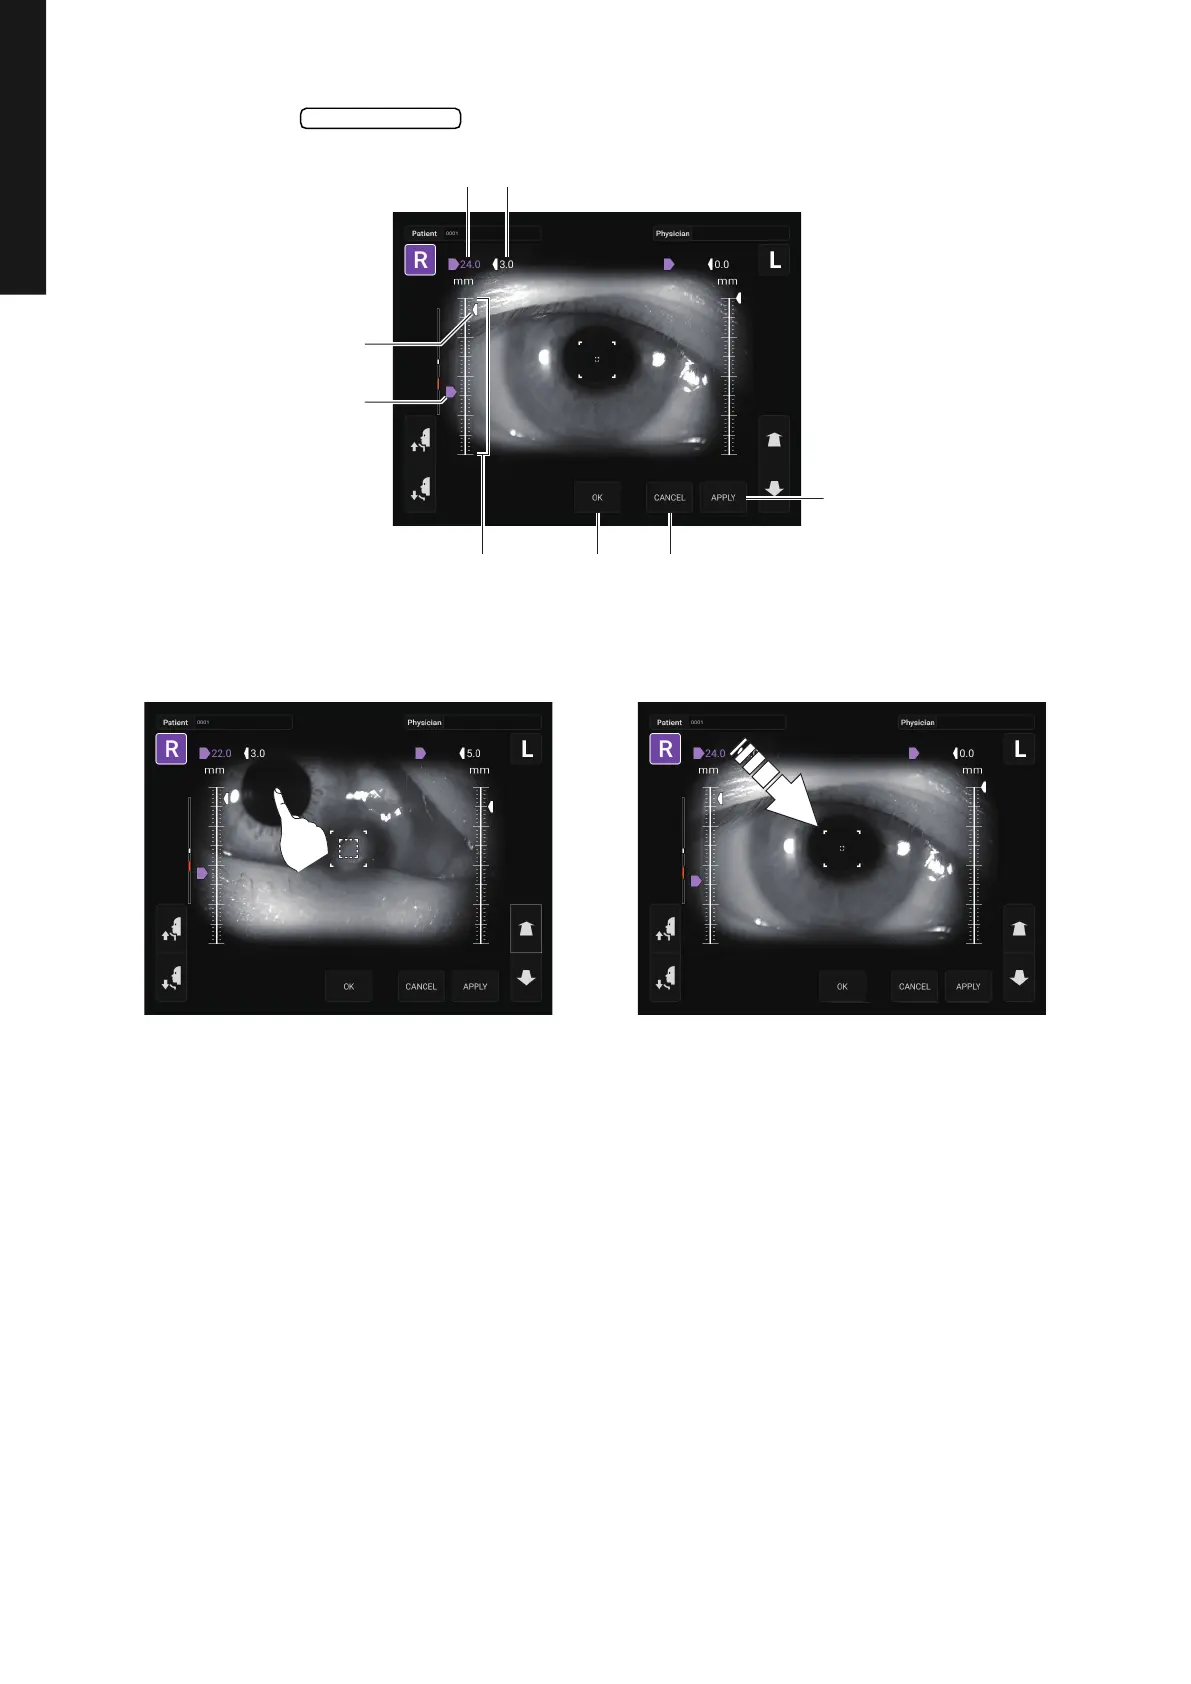

3 When the button is tapped, the Safety Stopper screen is called up.

4 Operating the control panel, set the center of the Measurement screen to the cornea center of

the patient.

Safety Stopper

APPLY button

CANCEL buttonOK buttonZ-axis operating range

Safety stopper icon

Z-axis position icon

Z-axis position Safety stopper position